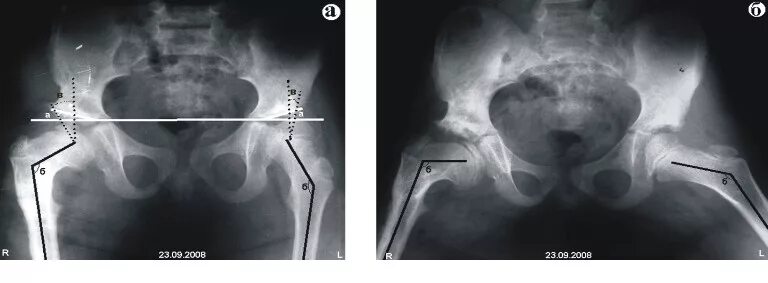

Рентген тазобедренный в двух проекциях